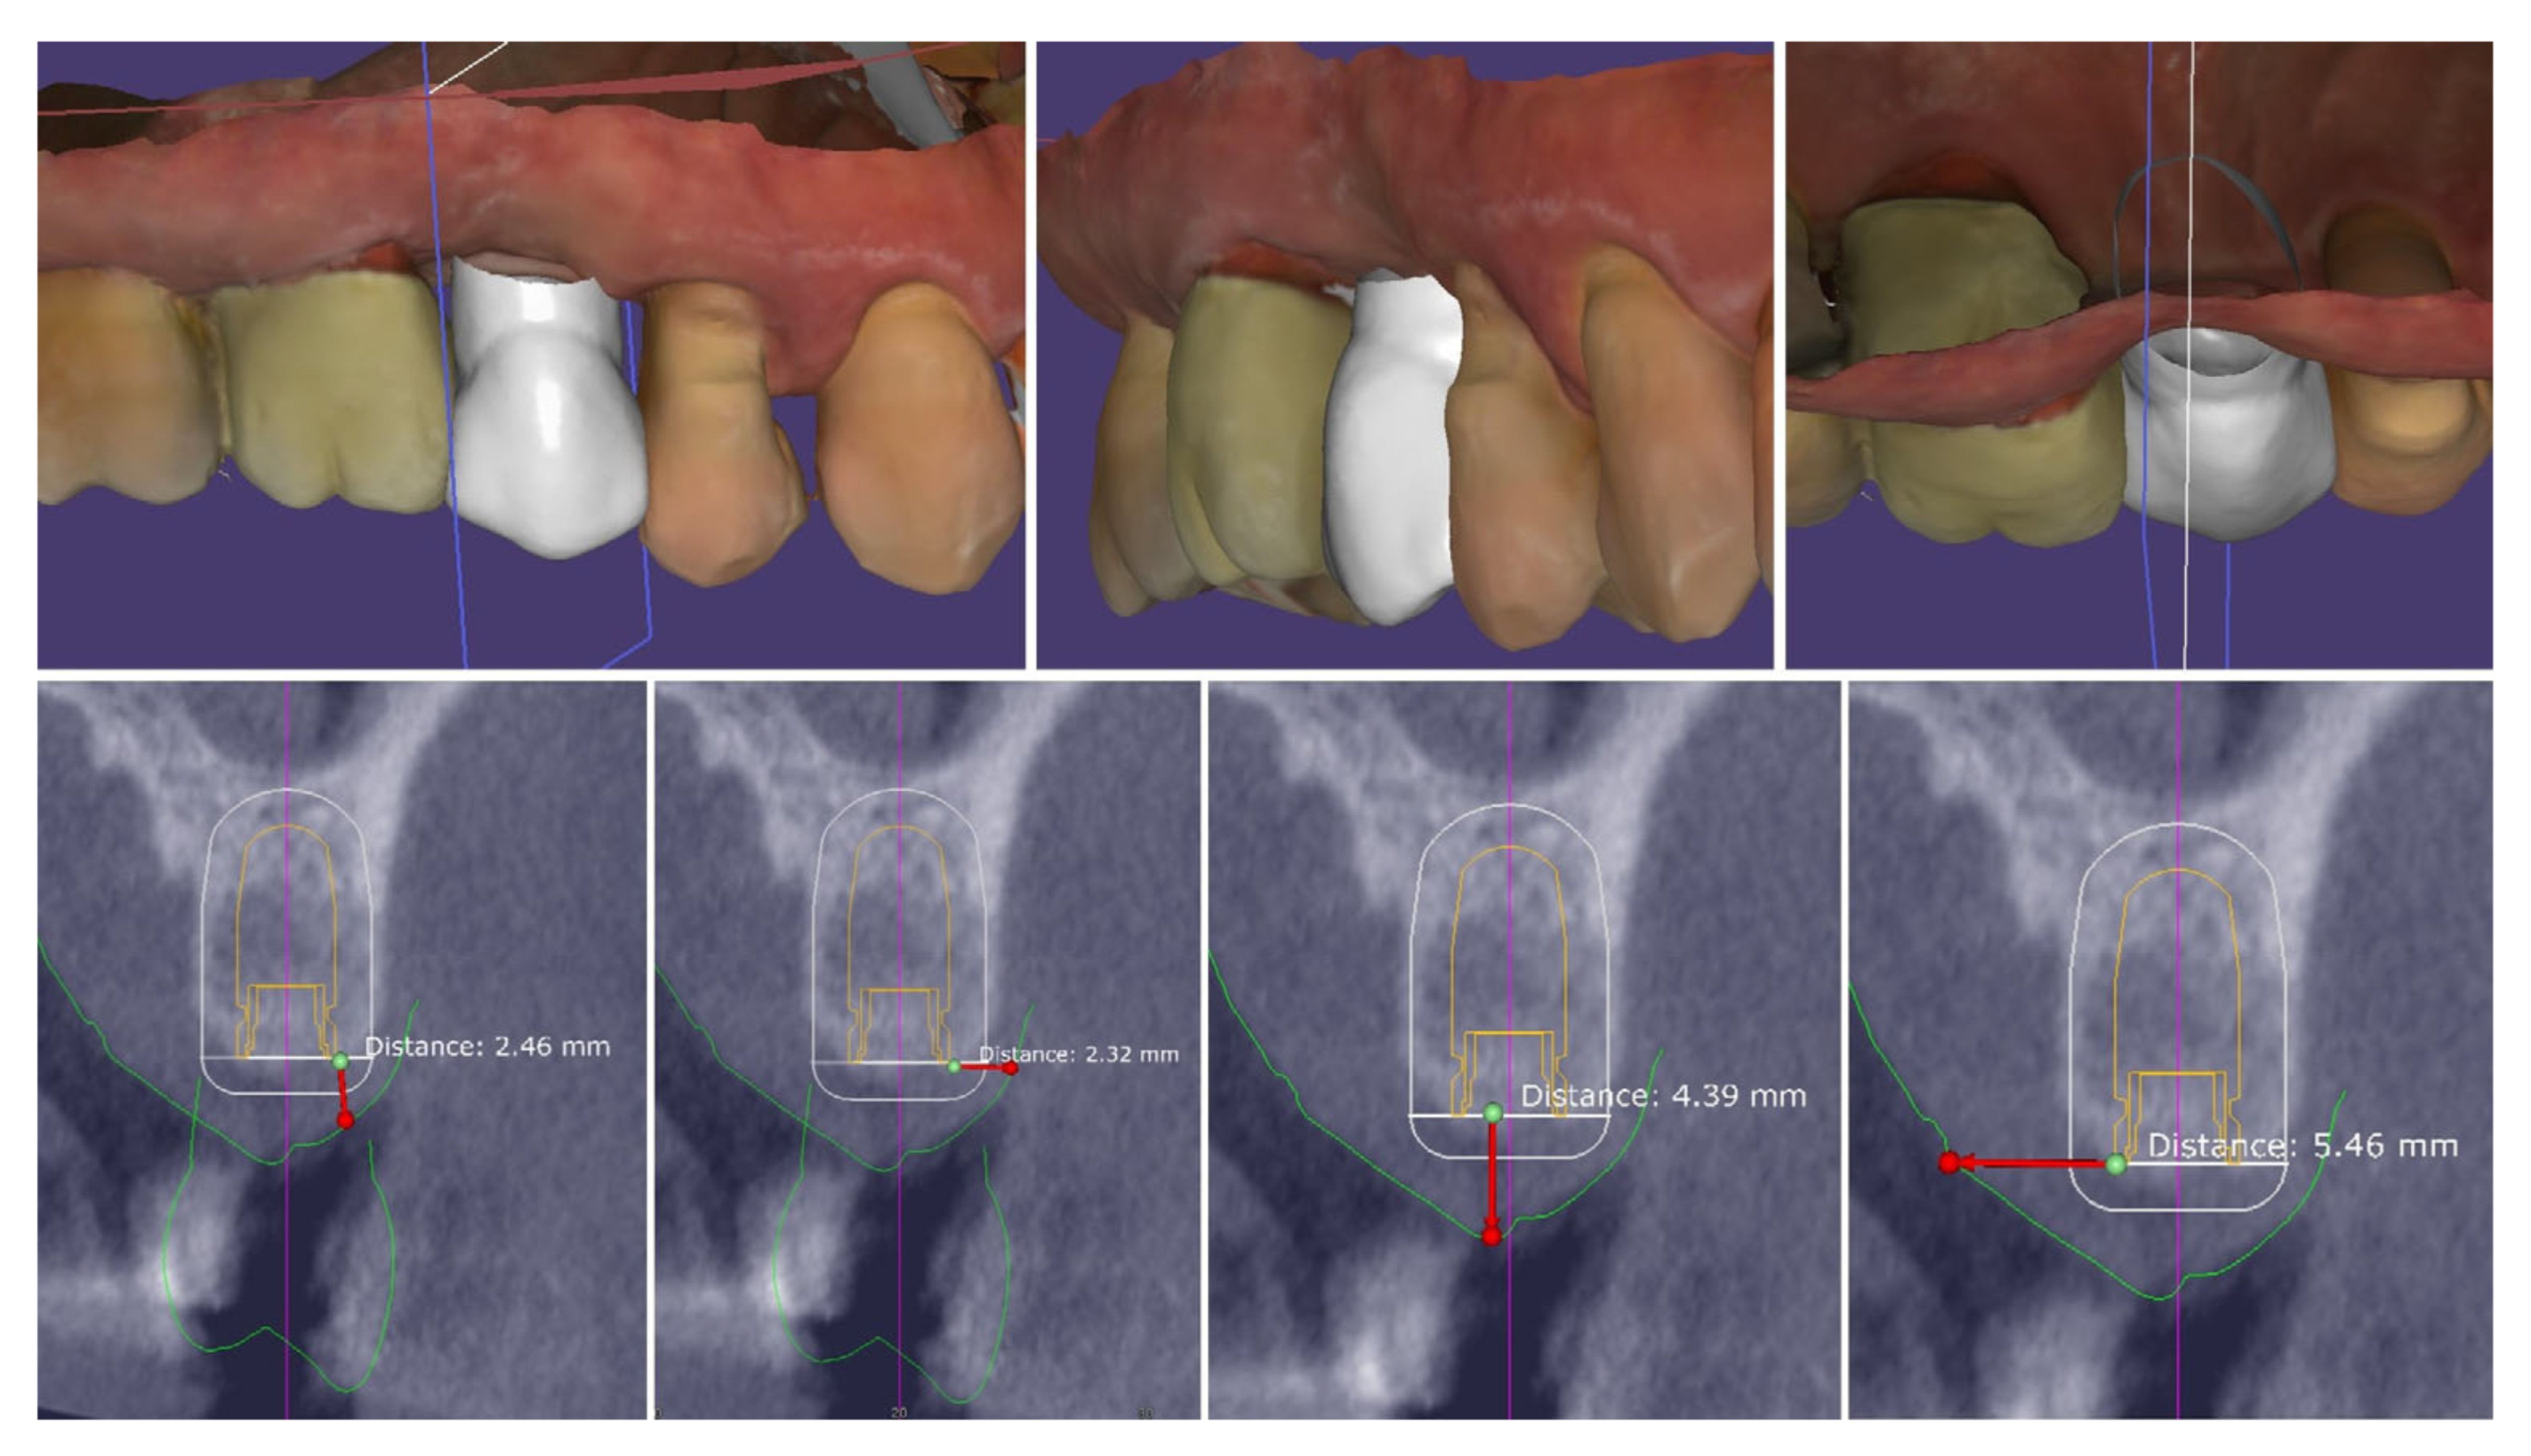

2. Materials and Methods—Clinical Case

- Bucco-lingual width of the crestal keratinized mucosa ≥ 4 mm;

- Mesio-distal width of the crestal mucosa (to the adjacent teeth)—∅ of the implant + min 3 mm;

- Height of the buccal keratinized mucosa ≥ 1 mm;

- Height of the palatal keratinized mucosa ≥ 3 mm;

- Thickness of the crestal mucosa ≥ 2 mm.